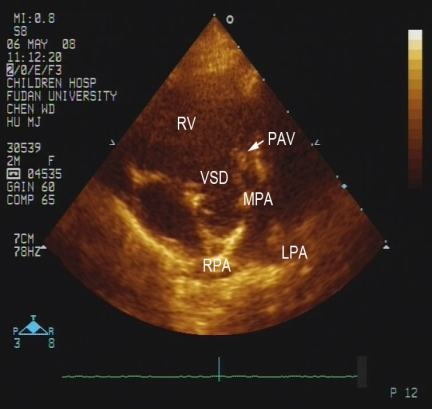

法洛四联症:超声心动图表现

室间隔缺损、主动脉骑跨

右室流出道狭窄